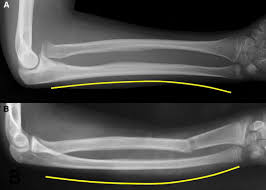

• Bowing Fracture

an incomplete fracture of tubular long pones that occur as a plastic response to longitudinal stress